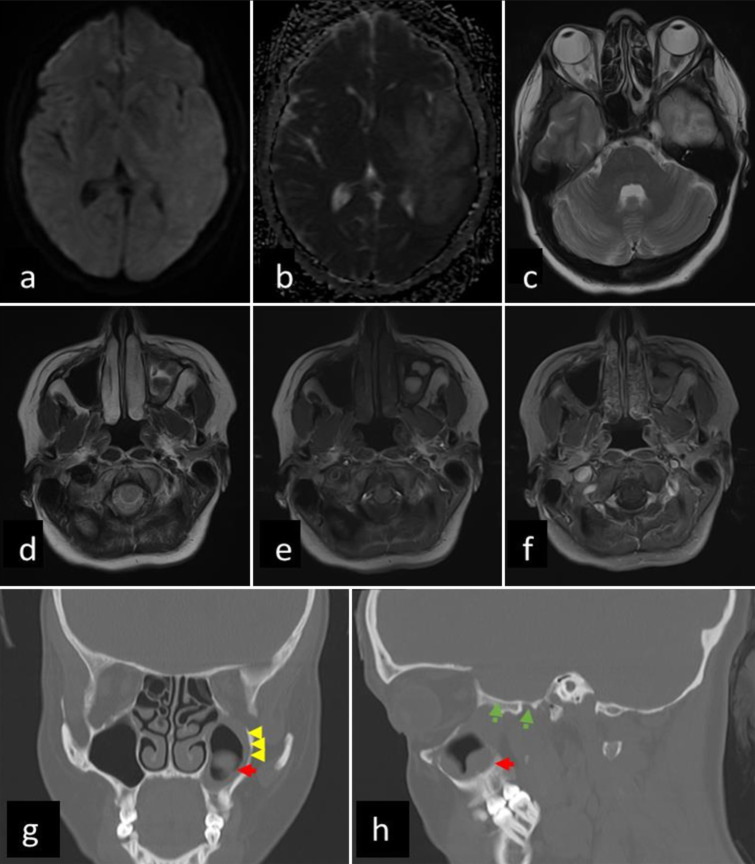

Case description: Herein, we report the presentation of a 34-year-old immunocompetent Pashtun female with acute-onset rapidly progressing generalized weakness, altered cognition, and motor and speech deficits. Although the radiological findings resembled a glioblastoma, the strong clinical suspicion of a fungal infection and her improvement on voriconazole treatment led to the decision to avoid surgical resection, thereby minimizing the risk of potential dissemination.